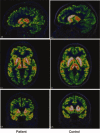

Huntington's disease (HD) is a neurodegenerative disorder, primarily affecting medium spiny neurones in the striatum. The density of striatal dopamine D(2) receptors is reduced in HD but there is little known about this biomarker in brain regions outside the striatum. The primary objective of this study was to compare extrastriatal dopamine D(2) receptor binding, in age-matched control subjects and patients with HD. All subjects were examined using a high-resolution positron emission tomography system and the high-affinity dopamine D(2) receptor radioligand [(11) C]FLB 457. A ROI based analysis was used with an atrophy correction method. Dopamine D(2) receptor binding potential was reduced in the striatum of patients with HD. Unlike the striatum, dopamine D(2) receptor binding in thalamic and cortical subregions was not significantly different from that in control subjects. A partial least square regression analysis which included binding potential values from all investigated cortical and subcortical regions revealed a significant model separating patients from controls, conclusively dependent on differences in striatal binding of the radioligand. Some clinical assessments correlated with striatal dopamine D(2) receptor binding, including severity of chorea and cognitive test performance. Hence, the present study demonstrates that dopamine D(2) receptors extrinsic to the striatum are well preserved in early to mid stage patients with HD. This observation may have implication for the development of therapy for HD.